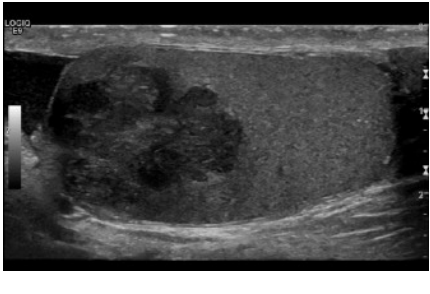

Sono appearance of seminoma?

Solid, hypoechoic or heterogeneous mass.